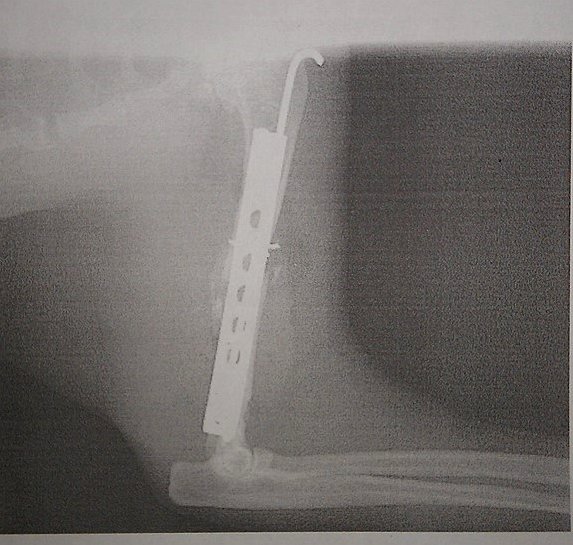

Katerchen ist seit der 2. OP ein Cyborg:

Katze.jpg

Katze.jpg (65.69 KiB) 3779 mal betrachtet

Seit gestern wohnt er bei meinem Bruder, in einem umgebauten Baby-Laufstall. Er darf jetzt erst mal 6 Wochen keine großen Sprünge machen.

Tierarztkosten bisher: Gut 750 Euro